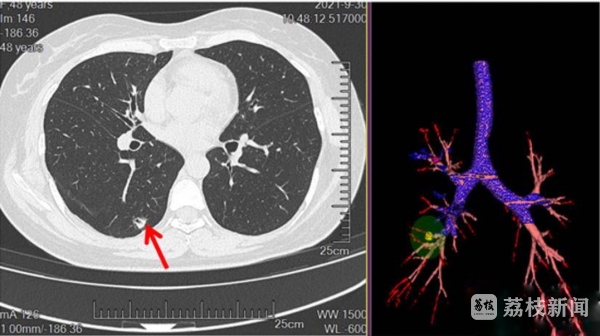

肺结节,在这年头已不是个让人陌生的医学名词。不少人都在体检中发现了“藏”在自己肺里的结节。48岁的方女士(化姓)最近就在一次手术前的CT检查和三维立体成像中被发现肺部右肺上叶前段、右肺下叶背段多发结节,可见分叶、毛刺、胸膜凹陷征象。

过去,碰上方女士这样的情况,手术方式可能选择胸腔镜右上肺前段切除+右肺下叶切除术。不过,切除较多肺组织可能会影响患者术后生存质量。如何能够既保证病灶的有效治疗,又减少患者的手术创伤,还能最大程度保留患者的肺功能呢?王涛主任团队经过研究,最终为方女士确定了消融+切除的一体化杂交手术治疗方案。王涛介绍,针对上叶前段结节,运用电磁导航气道内微波消融术以保留患者右上肺前段肺组织。针对下叶背段结节,运用电磁导航ICG定位联合胸腔镜下肺结节切除术。

记者了解到,医生在电磁导航引导下,引导支气管镜到达上叶前段病灶(腔外)位置,后放入消融针进行多段分次消融。消融结束后,支气管镜又通过电磁导航引导,到达下叶背段病灶位置,注射ICG(吲哚箐绿)染料进行标记,接着,在荧光胸腔镜下探查染色标记位置,对病灶完成胸腔镜下肺结节切除。

这样的操作在完整切除病灶的前提下,还尽可能保留了正常肺组织。手术后,方女士顺利恢复,术后24小时复查胸部CT显示右上肺前段结节(即消融结节)处未见结节影,原肺结节已瘢痕化,治疗效果满意。